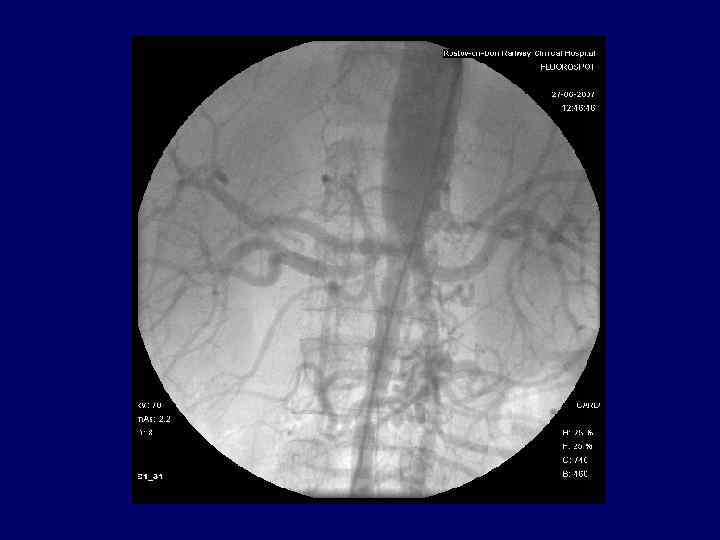

Инструментальные методы 1. 2. 3. 4. 5. УЗ – доплерография артерий КТ с контрастированием МРТ в ангиографическом режиме R – органов грудной клетки Аортоангиография

А. Неравномерное снижение кровотока и сужение просвета левой подключичной артерии при болезни Такаясу В. Классический симптом "четок": множественные аневризмы сосудов у больного, страдающего изолированным васкулитом ЦНС.